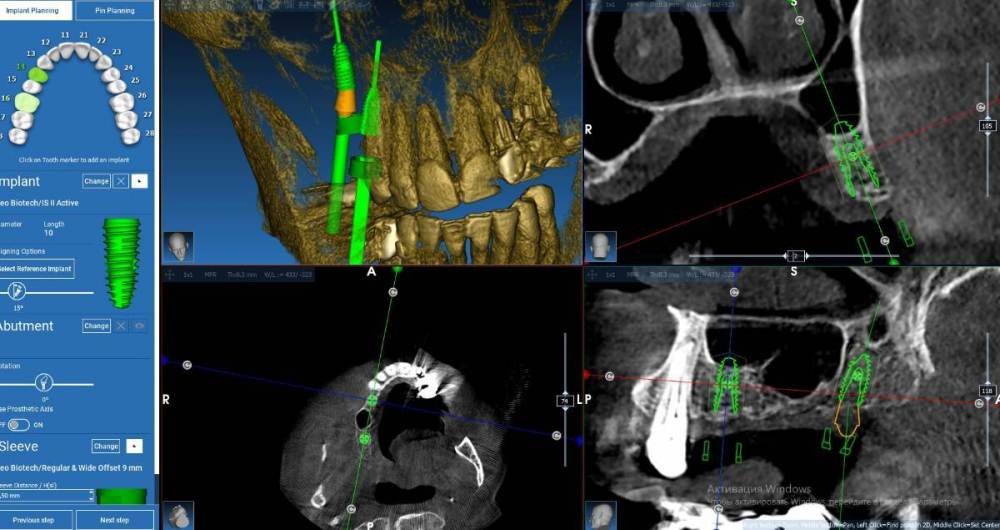

Fin Опубликовано 5 марта, 2023 Поделиться Опубликовано 5 марта, 2023 Например вот так Ссылка на комментарий